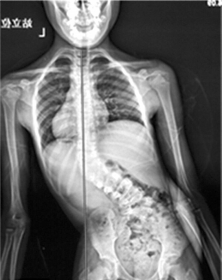

术前X片显示小佳(化名)的躯干明显倾斜。

小佳(化名)是一名来自郴州的9岁女孩,3岁时被诊断患有严重的先天性脊柱侧凸,胸12及腰5各有一个半椎体。多年来,父母带着小佳走遍了省内各家医院,但皆因年龄太小,手术难度大、风险高而没有能解除疾苦。

随着小佳的年龄增长,脊柱侧凸越来越严重,并出现骨盆倾斜,行走不稳。小佳的父母经多方打听,带她来到湘雅医院就诊。